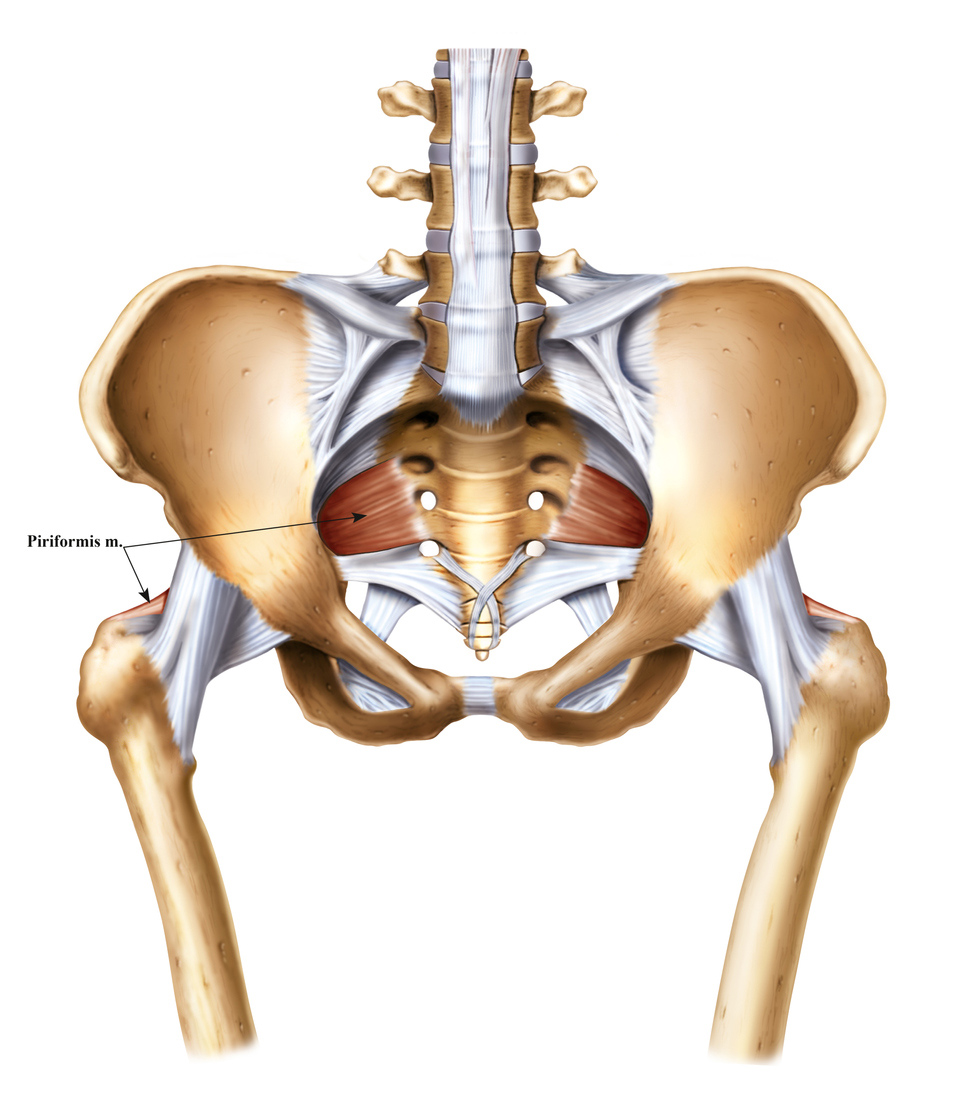

Анатомия мышц: Пириформис

:max_bytes(150000):strip_icc()/human-muscles-illustration-605384917-57ac6b9c3df78cf4597a56f4.jpg)